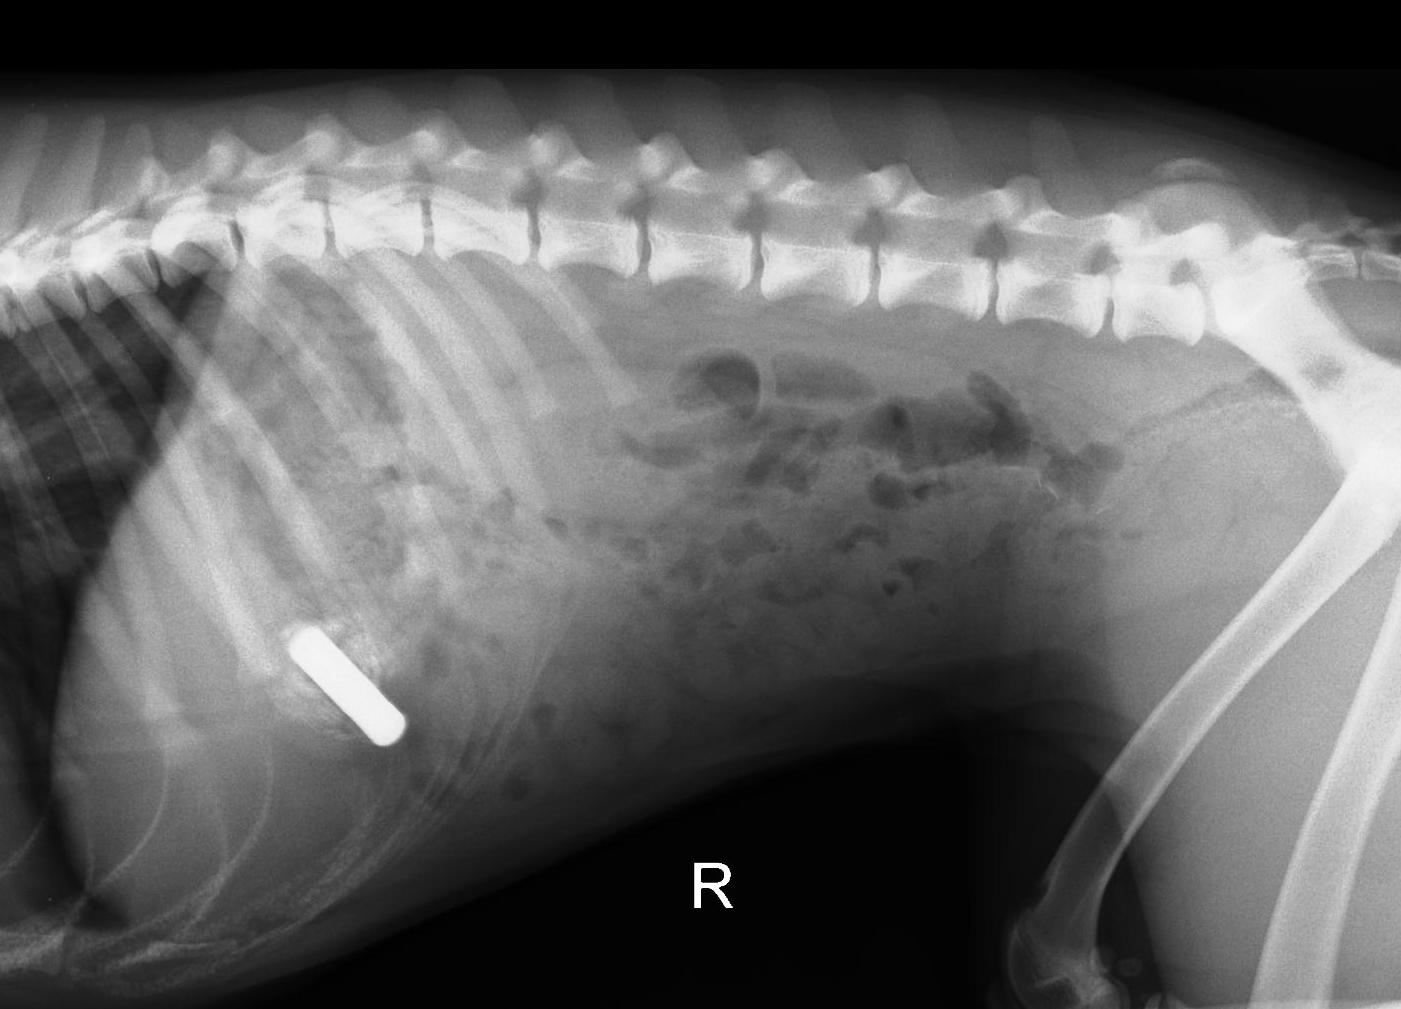

הוחלט לבצע צילום רנטגן ואז, כמובן, נמצאה הסוללה החסרה בקיבתה של הכלבה.

הפעם הוחלט, שמכיוון שמדובר בסוללה לא גדולה במיוחד, שננסה גרימת הקאה, במידה והסוללה לא תיצא או שתתקע בוושט תבוצע שוב אנדוסקופיה (מכיוון שסוללה יכולה להפריש חומרים רעילים ומסוכנים, אסור להשאירה בגוף ולחכות שתצא). הכלבה קיבלה זריקה הגורמת להקאה, ולמזלה, ולשמחת הבעלים, הסוללה יצאה ללא כל בעיה.